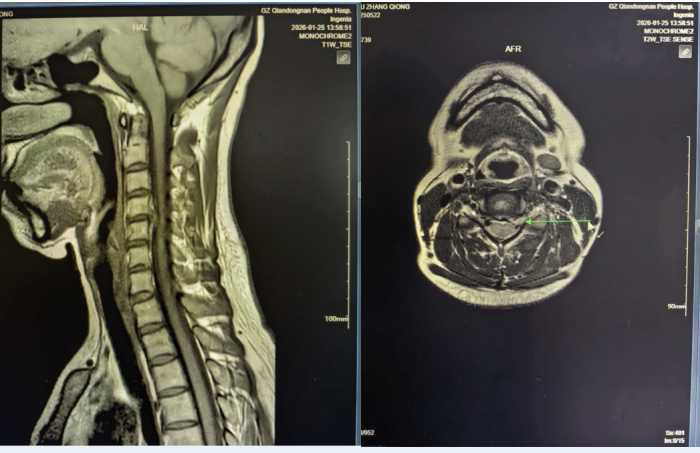

术前影像